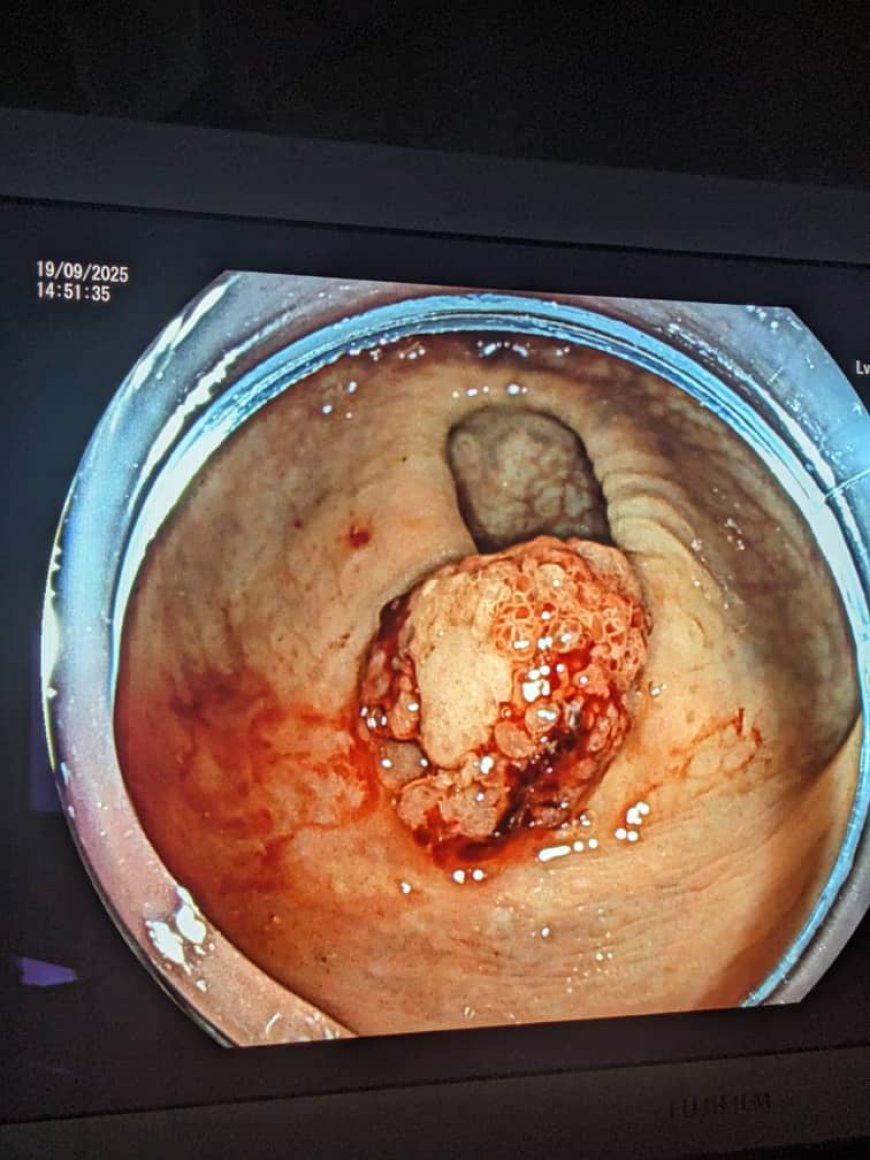

Abaganga b’inzobere bo mu Bitaro byitiriwe Umwami Faisal i Kigali babashije gukura mu mubiri w’umuntu agace gafite kanseri mu rura runini batamubaze nk’uko byari bisanzwe, ahubwo hakoreshejwe ikoranabuhanga rya ‘Endoscopic Submucosal Dissection (ESD)’.

Mu butumwa ibi bitaro byanyujije ku rubuga rwa X bugira buti “Itsinda ryacu ryabashije bwa mbere gukura kanseri ikiri ntoya mu rura runini. Ibi byarinze uwo murwayi ko habaho gushiririza iyo kanseri cyangwa kubaga urura rwe runini ngo ajye yitumira ahandi.”

ESD ni uburyo bwo gukura igice gifite kanseri ikiri ku rwego rwo hasi mu myanya igize urwungano ngogozi nko mu gifu, urura runini n’ibindi bice hatabayeho kubibaga.

Ubu buryo bukoreshwa mu kuvura kanseri ikiri ntoya itaratangira gukwirakira mu rugingo yafashe.